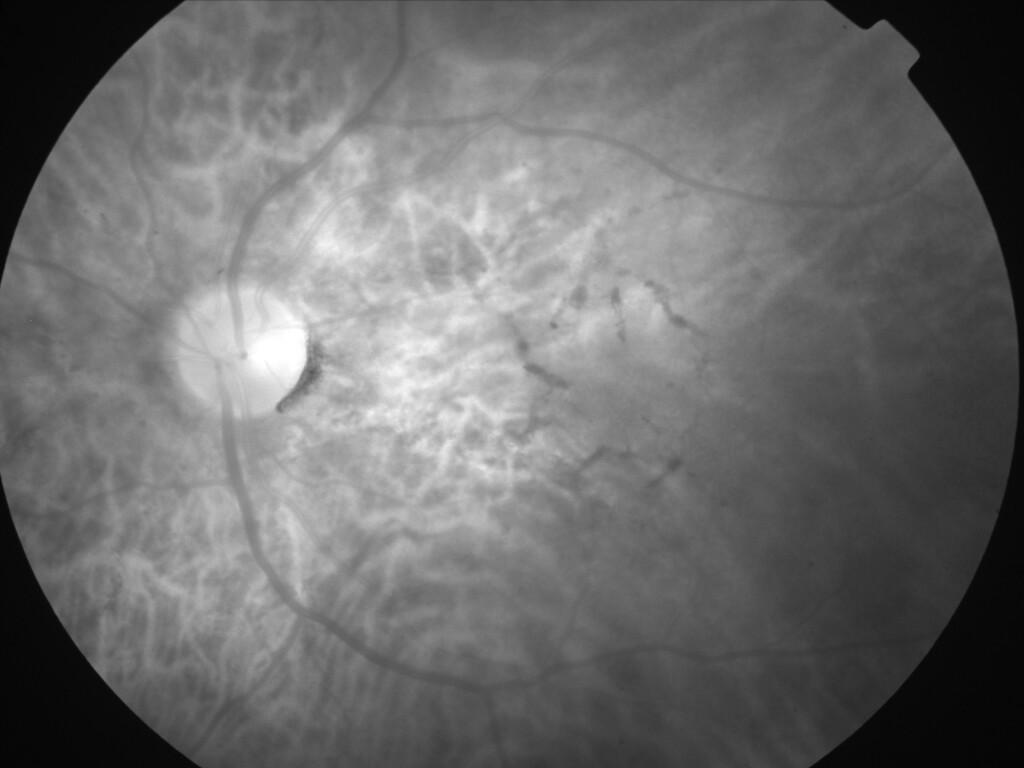

ASSOCIATION STRIES ANGIOIDES ET DYSROPHIE MACULAIRE RETICULEE

NEOVASCULARISATION